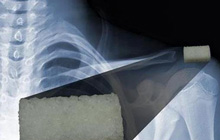

未来这几年,全世界的外科手术将植入成千上万3D打印的髋骨、膝盖骨、踝骨、部分脊柱甚至颅骨的替代假体。它们中的大多数看起来和传统的钛合金植入假体非常相像,但是这些最早的根据个体解剖学数据3D打印的植入体,终将会开启骨骼替代品订做普及的新时代。

3D打印技术正迅速成为植入物行业的一个重要部分,并通过可量身定制的3D打印植入物在这一领域里掀起一场革命。不过,尽管如此,这个领域中的最大问题,如何解决人体排异反应问题仍然没有得到根本的解决。